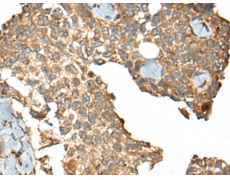

IHC positive control: |

Human ovarian cancer and human esophagus cancer |

IHC Recommend dilution: |

30-150 |